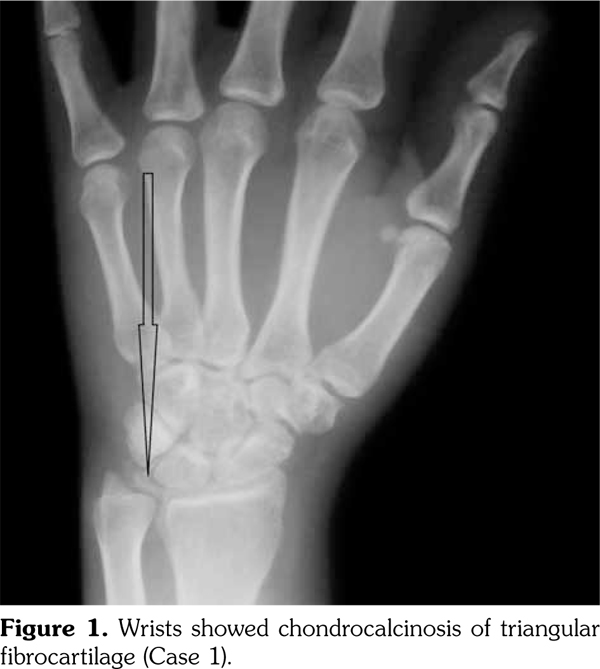

On examination, there was swelling and painful restriction of movement in her right knee. Imaging revealed calcification of cartilage of wrists, knee joints and hip joints although no microscopic confirmation was possible at this stage (Figure 1-4). She was investigated for a possible cause for CC, although investigations to screen for a metabolic cause turned out to be negative with a possibility for hereditary CC.

Case 1- A 35-year-old female patient was admitted to the hospital with an episode of community acquired pneumonia. During her stay at the hospital, she developed a right knee joint pain and an effusion. Joint sepsis was excluded by an orthopedic surgeon. However, during her stay, she complained of pain in both knees and wrist joints needing a rheumatology consultation.

She gave a history of recurrent pain and swelling of her right knee joint and wrists for the past five years and was treated symptomatically by a general practitioner. These episodes were self- limiting and resolved usually within two to three weeks. There was a family history of her father and younger sister having similar problems and her father (64 years old) was being followed-up at the clinic for CC. A written informed consent was obtained from the patient.